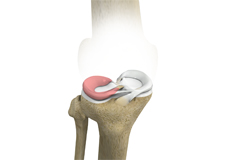

Articular Cartilage and Menisci of the Knee

Movement of the bones causes friction between the articulating surfaces. To reduce this friction, all articulating surfaces involved in the movement are covered with a white, shiny, slippery layer called articular cartilage. The articulating surface of the femoral condyles, tibial plateaus and the back of the patella are covered with this cartilage. The cartilage provides a smooth surface that facilitates easy movement.

To further reduce friction between the articulating surfaces of the bones, the knee joint is lined by a synovial membrane that produces a thick clear fluid called synovial fluid. This fluid lubricates and nourishes the cartilage and bones inside the joint capsule.

Within the knee joint, between the femur and tibia, are two C-shaped cartilaginous structures called menisci. Menisci function to provide stability to the knee by spreading the weight of the upper body across the whole surface of the tibial plateau. The menisci help in load-bearing i.e. it prevents the weight from concentrating onto a small area, which could damage the articular cartilage. The menisci also act as a cushion between the femur and tibia by absorbing the shock produced by activities such as walking, running and jumping.